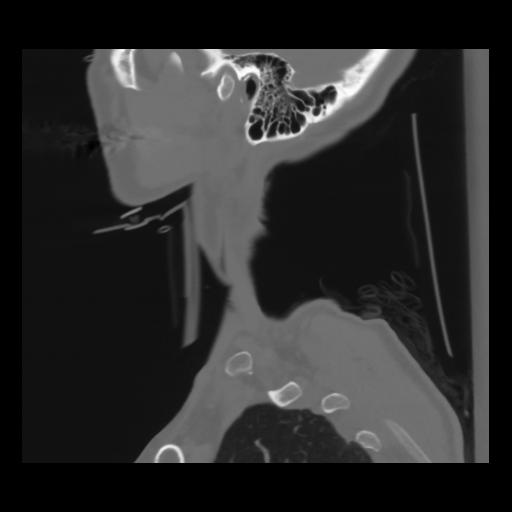

14 P.BLANDAS,,Sagittal,2.000,P.BLANDAS,Sagittal,